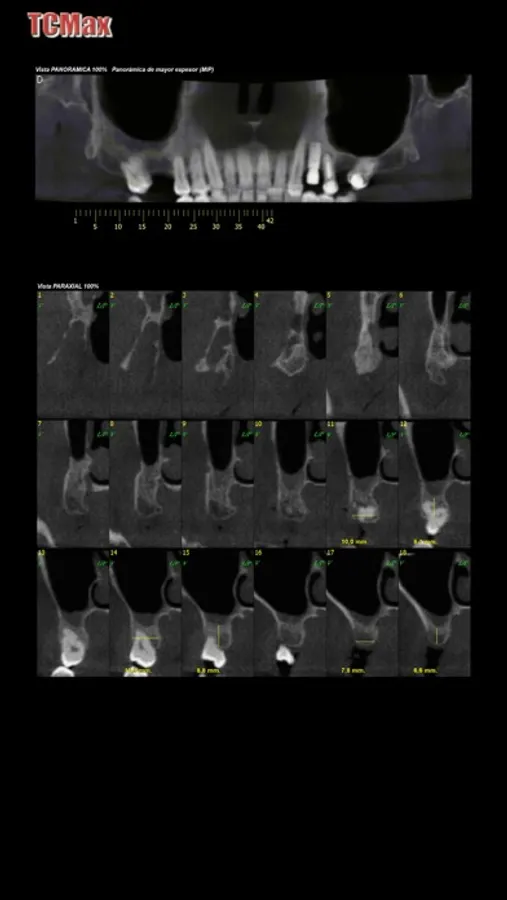

App para la visualizacion de estudios radiograficos dentales TCMax

Tcmax Screenshots